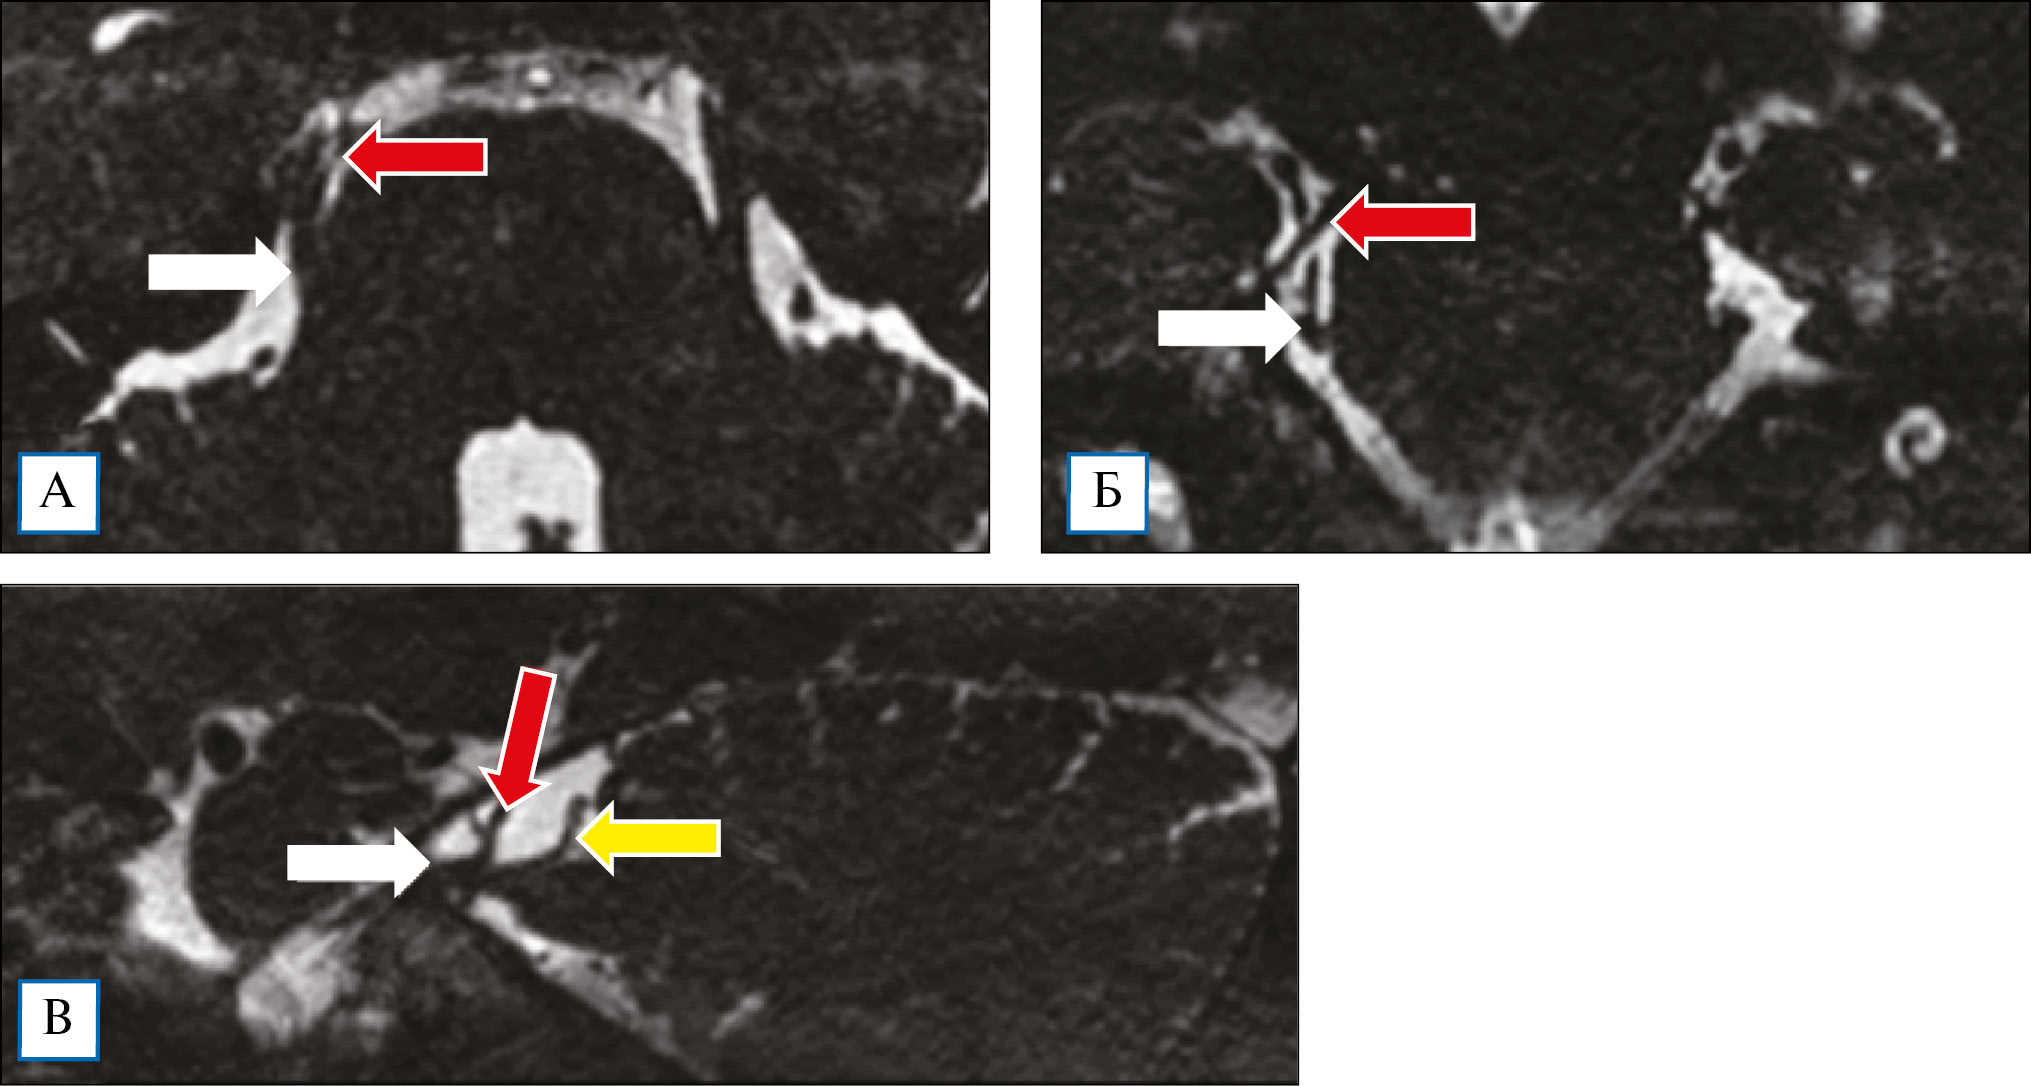

После клинического осмотра наличие нейроваскулярного конфликта подтверждали с помощью МРТ головного мозга на аппарате мощностью 1,5–3 Тесла в режиме 3D — CISS, или FIESTA, или DRIVE. Во всех случаях был выявлен нейроваскулярный конфликт между верхней мозжечковой артерией и/или веной и корешком тройничного нерва, у 35 (56,5%) пациентов отмечено уменьшение площади поперечного сечения нерва (рис. 1). Другая нейрохирургическая патология исключена.

Рис. 1. Пациент М. с невралгией тройничного нерва: магнитно-резонансная томография головного мозга в режиме FIESTA

Примечание. На томограммах в режиме FIESTA в аксиальной (А), фронтальной (Б) и сагиттальной (В) плоскостях определяется сдавление тройничного нерва (стрелка белого цвета) верхней мозжечковой артерией (стрелка красного цвета) и веной (стрелка желтого цвета).